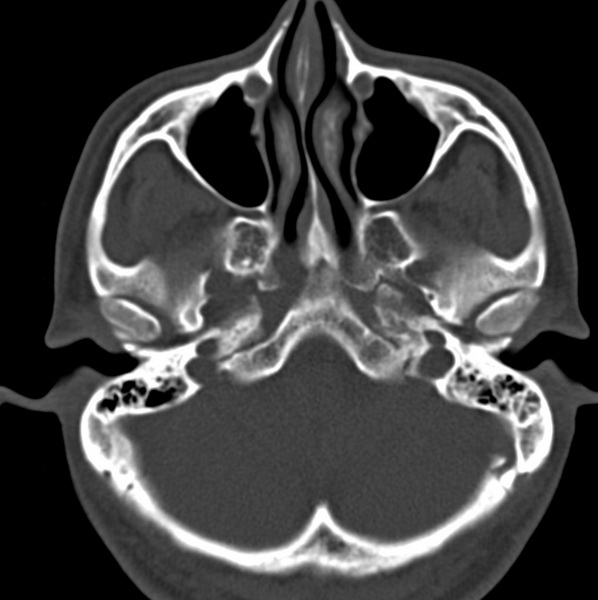

男、31、鼻咽部肿瘤放疗后请帮忙看看。

效果好,右侧破裂孔扩大,局部骨质缺损,为颅底骨质破坏。

1)鼻咽部肿瘤侵犯颅底放疗术后改变。2)左侧蝶窦炎。

咽后壁增厚,左侧咽鼓管隆突增大、咽鼓管咽口变浅,同侧咽旁间隙较窄。右侧颅底骨质破坏?为什么不在同一侧?

鼻咽部肿瘤侵犯颅底放疗术后改变.